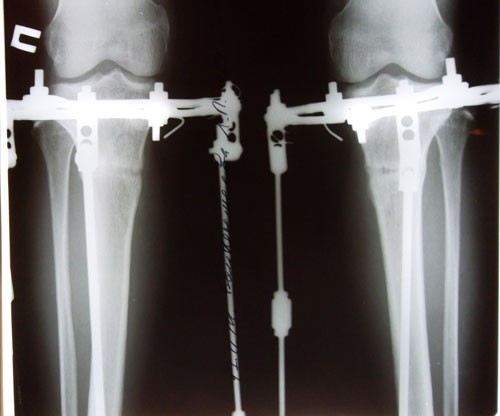

Последние штрихи.